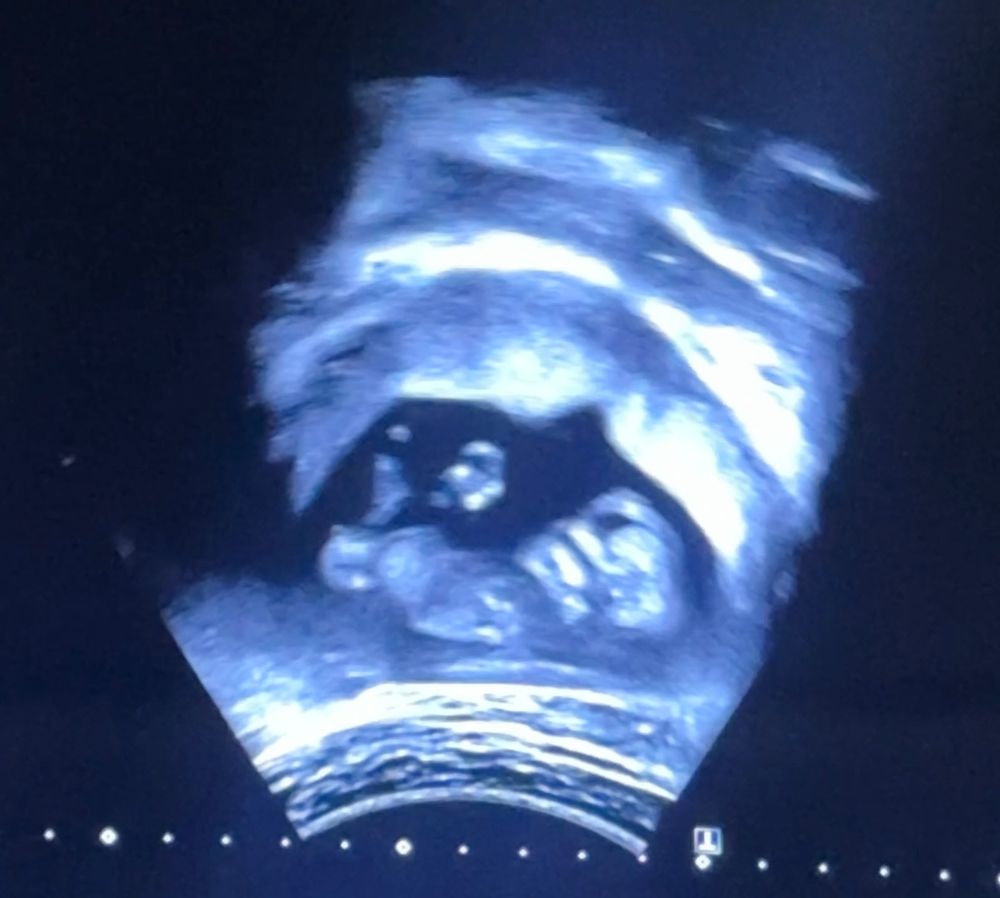

Таня в Клуб беременных 10 месяцев Пол малыша УЗИ, КТГ, доплер Получилось обнаружить ещё такой скрин, 12.4 недели, тут видно пол? Посмотрите еще 20 записей на эту тему Отменить Ответить В ожидании чуда Девочка 02.02.2025 Ответить Юлька Если это действительно бугорок, то девочка должна быть 02.02.2025 Ответить Kamila E Девочка, но еще всë может поменяться и таких случаев куча 02.02.2025 Ответить Алёна Хаустова Предположу, что девочка 02.02.2025 Ответить Юлия Мать Драконов девочка 02.02.2025 Ответить Утолщение плацены Метод Нуб Чаты Беременных Выберите чат: Январята-2026 Февралята-2026 Мартята-2026 Апрелята-2026 Майчата-2026 Июнята-2026 Июлята-2026 Августята-2026